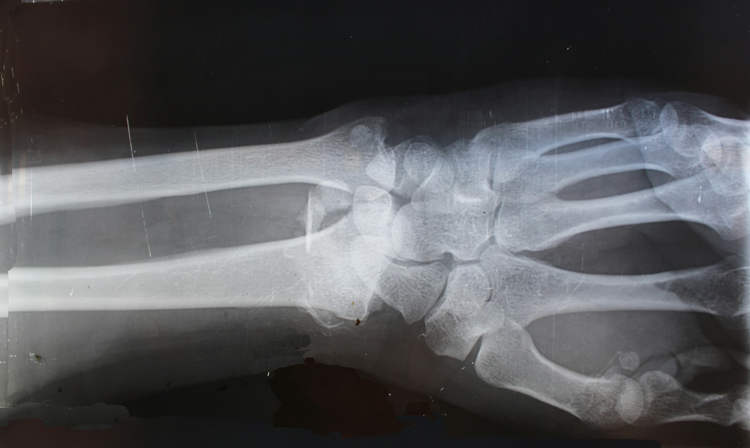

Bone-02 уже протестирован более чем в 150 клинических случаях. Один из пациентов смог обойтись без установки металлической пластины в запястье — кость полностью срослась после трёхминутной процедуры и трёх месяцев наблюдения.